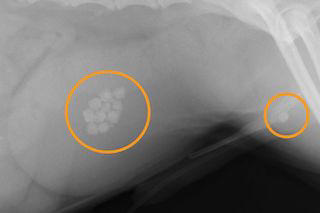

膀胱結石 北千里動物病院 大阪府箕面市

泌尿器系の病気 ー 尿石症 シュウ酸カルシウム結石の例 院長ブログ うぇる動物病院 町田市本町田の動物病院 犬猫の予防接種 夜間診療 ペットホテル

膀胱結石 整形外科 心臓内科の症例集 犬 猫の整形外科の治療はみどり動物病院

膀胱結石による尿道閉塞 京都市で動物の手術なら当院へ 西京極どうぶつ病院

犬の膀胱結石と腹腔鏡下摘出術 Info クウ動物病院 動物内視鏡医療センター